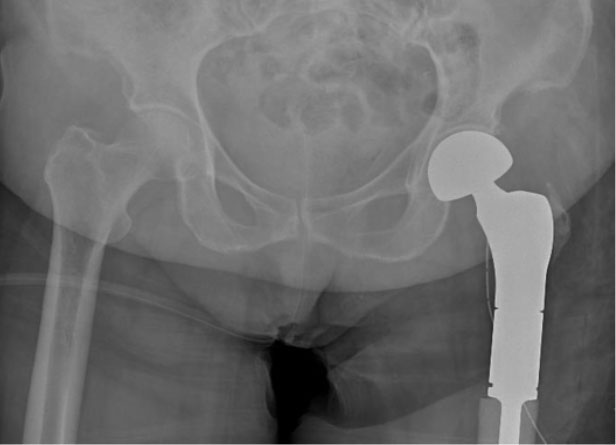

Ameliyat sonrası: Röntgende proksimal femur rezeksiyonu ve tümör protezi görülmekte